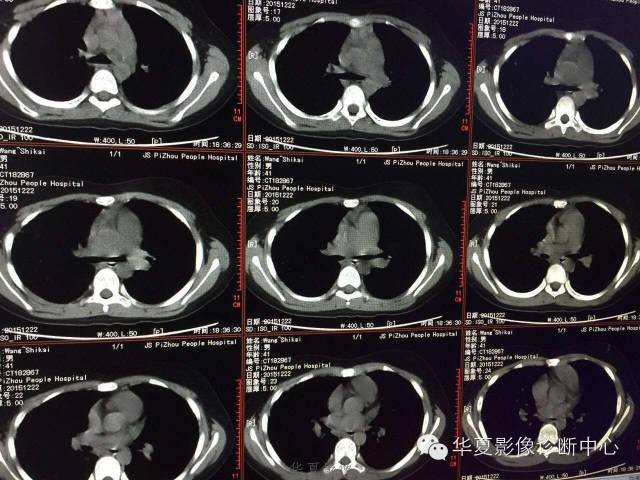

支原体肺炎1例CT影像表现